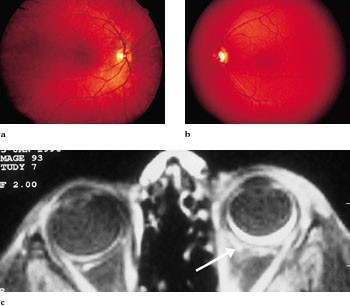

Nevus flammeus er medfødte, kutane, vaskulære malformasjoner (fig 1) som affiserer 0,3 % av nyfødte (1). Fødselsmerkene er ofte distribuert svarende til dermatomer, og kan representere mosaikker oppstått i nevralrøret (2). Barn med nevus flammeus i trigeminusområdet kan ha intraokulære vaskulære forandringer (fig 2) og økt risiko for utvikling av glaukom og permanent synssvekkelse i ung alder (2). Barna bør derfor følges i et strukturert system for øyeundersøkelse og oppfølging.

Koroidale hemangiomer har vært den vanlige betegnelsen på karforandringer påvist i choroidea hos pasienter med fødselsmerke. Nomenklaturen har dessverre vært forvirrende. Medfødte vaskulære forandringer skal i dag benevnes vaskulære malformasjoner, mens hemangiomer er forbeholdt vaskulære lesjoner med rask neonatal vekst (6). Nevus flammeus er en vaskulær malformasjon, og vi har derfor valgt å kalle den av og til ledsagende forandring i choroidea for koroidal vaskulær malformasjon.

Vi fant koroidal vaskulær anomali hos sju barn. Dette er en høyere andel enn hva Stevenson & Morin rapporterte (4). De undersøkte 50 barn med oftalmoskopi, dog uten rutinemessig bruk av anestesi. Dette kan ha medført en underrapportering. Forfatterne hevder i sin artikkel at nevus flammeus som er lokalisert alene til øvre eller midtre trigeminusgren, ikke synes å være assosiert til glaukom. Vi fant koroidal vaskulær malformasjon hos barn med kun øvre trigeminusgren/øvre øyelokk affisert. Selv om disse barna ikke hadde glaukom, tror vi det er sannsynlig at også disse barna har økt risiko for å utvikle glaukom.